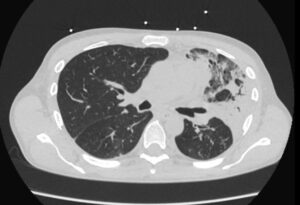

A 52-year old man with a history of diffuse large B cell lymphoma in remission presented with 3 weeks of shortness of breath, cough, fever, and shock. Electrocardiogram revealed sinus tachycardia, diffuse ST segment elevations, PR segment depression, prolonged QTc, and electrical alternans. Bedside echocardiogram was performed, revealing a large circumferential pericardial effusion with tamponade physiology. The patient underwent echo-guided pericardiocentesis with drainage of 400 ml of purulent fluid. Pericardial and blood cultures were positive for Haemophilus influenzae. A CT of the chest was indicative of empyema. Given the patient’s history of rituximab use, autologous stem cell transplant, and profound infection, immunoglobulin levels were drawn and found to be undetectable. The patient received 6 weeks of intravenous antibiotics with IVIG infusions. He was treated with colchicine and aspirin for purulent pericarditis. Two months later, a cardiac MRI was performed, which revealed resolution of the pericardial effusion. No evidence of constrictive pericarditis was noted on MRI, but continued pericardial enhancement was observed. Colchicine was continued for an additional 3 months. The patient made a full recovery at 6 month follow up.